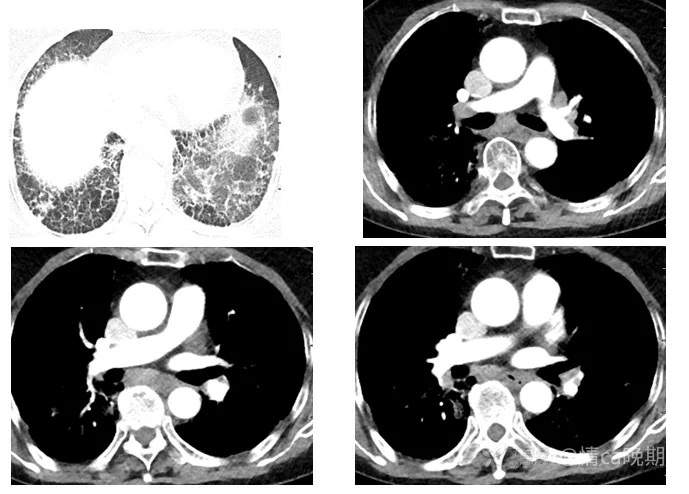

CTA(2023-2-8): 1. 双肺见散在斑片状、片状、条索状密度增高影,双肺胸膜下及双肺下叶肺组织呈网格状改变,考虑肺间质纤维化并炎症;2.左上、下肺动脉起始处可见少许条形充盈缺损影。

2023年2月10日PET-CT: 1.全身PET-CT扫描未见确切恶性肿瘤征象。2.双肺胸膜下网格状改变,双肺多发斑片状密度增高影并代谢增高,考虑为双肺间质性炎。3.右肺上叶及左肺下叶小结节,代谢未见增高,考虑为慢性炎性结节。双肺上中叶及左肺下叶钙化灶。4.纵隔1R/L、2R/L、4R/L、7、10R稍大淋巴结,部分密度稍高,放射性摄取增高,SUVmax约为5.8,考虑为慢性炎性淋巴结。5. 胃窦壁增厚,放射性摄取增高,SUVmax约为3.3 ,考虑炎性病变或生理性摄取。6.双侧臀部皮下脂肪间隙内絮状密度影并代谢增高,右侧肩关节周围组织代谢增高,考虑为炎性病变。7.右前臂局灶性放射性摄取浓聚,考虑为放射性药物沾染。